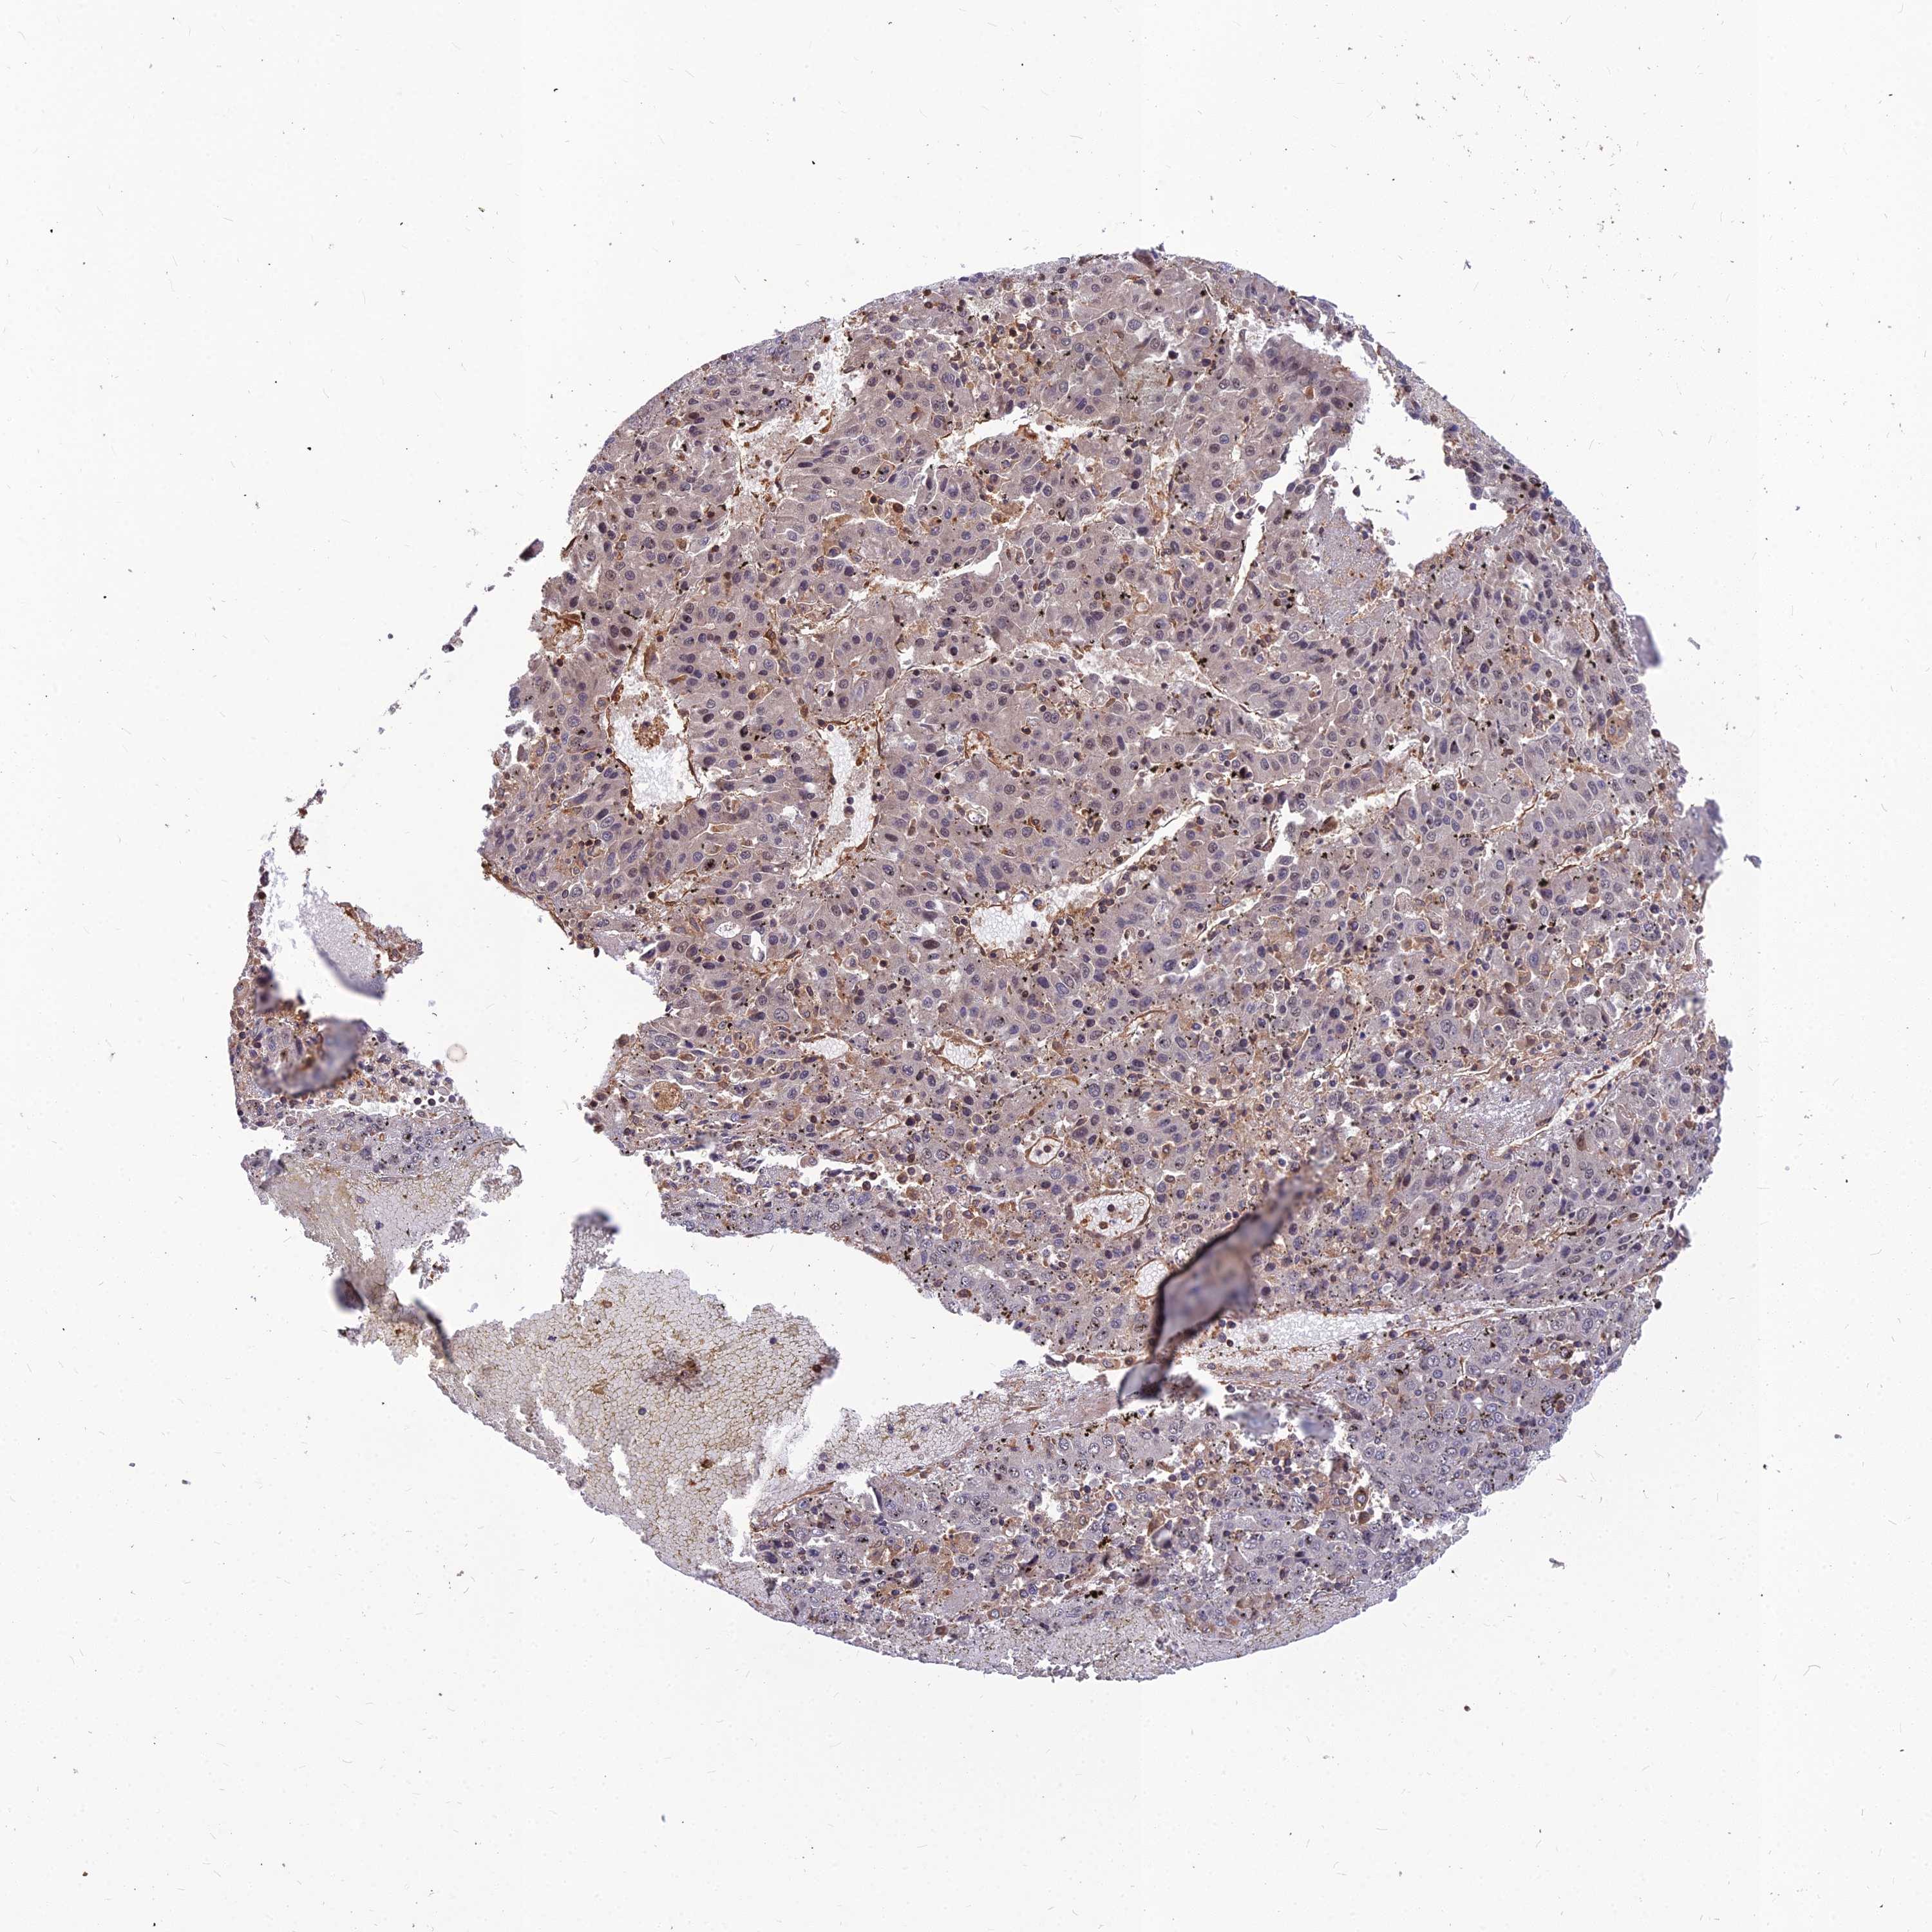

LIVER CANCER - Protein expressioni

A mouse-over function shows sample information and annotation data. Click on an image to view it in a full screen mode. Samples can be filtered based on level of antibody staining by selecting one or several of the following categories: high, medium, low and not detected. The assay and annotation is described here.

Note that samples used for immunohistochemistry by the Human Protein Atlas do not correspond to samples in the TCGA dataset.

Antibody stainingi

Antibody staining in the annotated cell types in the current human tissue is reported as not detected, low, medium, or high, based on conventional immunohistochemistry profiling in selected tissues. This score is based on the combination of the staining intensity and fraction of stained cells.

Each image is clickable and will lead to virtual microscopy that enables deeper exploration of all samples and also displays staining intensity scores, fraction scores and subcellular localization as well as patient and tissue information for each sample.

Antibody HPA042907

Staining

High

Medium

Low

Not detected

Intensity

Strong

Moderate

Weak

Negative

Quantity

>75%

75%-25%

<25%

None

Location

Nuclear

Cytoplasmic/membranous

Cytoplasmic/membranous,nuclear

Cholangiocarcinoma

Carcinoma, Hepatocellular, NOS